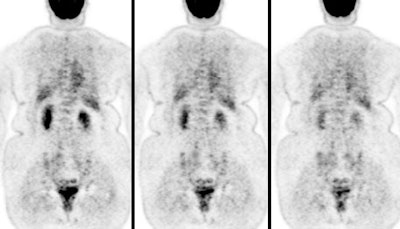

Monitoring response to therapy: The patient shown below had received chemotherapy for treatment of metastatic breast cancer (pre-therapy scan is on the left). The post-therapy scan (right image) demonstrated a very good response to treatment, however, several foci of tracer uptake remained (black arrows) consistent with residual metastatic disease. Further therapy was planned as a result of the PET scan. |

|